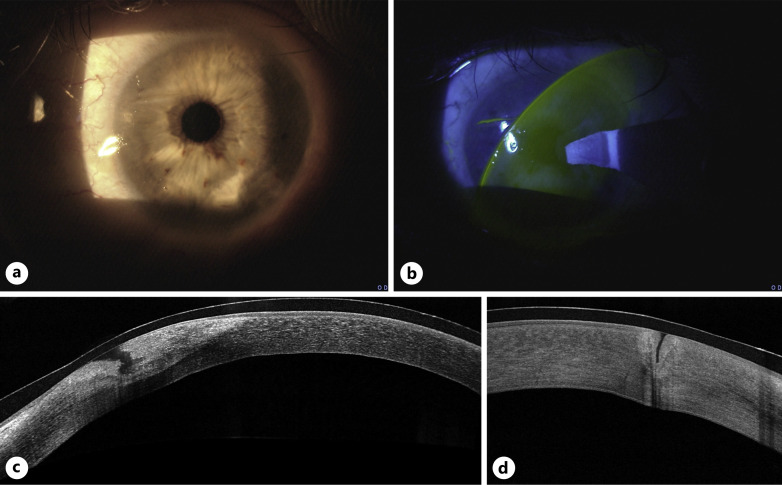

Case description: A 75-year-old man presented with unilateral diathermy-associated corneal laceration superior to the visual axis following cosmetic blepharoplasty. Vision had deteriorated from his baseline 20/30 to 20/125 postoperatively. Intervention involved multilayer AMT alongside standard care, including topical steroids and antibiotics, oral doxycycline, and vitamin C. Postoperative course was monitored with anterior segment optical coherence tomography (AS-OCT) imaging. By 3 months, complete corneal healing and restoration of baseline visual acuity were achieved.